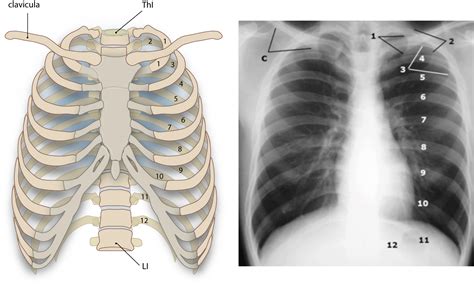

Let’s get down to the nitty-gritty of the os clavicula ’s anatomy, guys. The collarbone is a slender, S-shaped bone that sits right on top of your rib cage, just beneath your skin. It’s one of the most frequently fractured bones in the body, especially in active individuals, so knowing its structure is key. It has two main ends: the sternal end and the acromial end . The sternal end, the medial part, connects to the manubrium of the sternum (your breastbone) at the sternoclavicular joint. This joint is pretty special because it’s one of the few places where a long bone articulates with the axial skeleton. The acromial end, the lateral part, connects to the acromion, which is part of the scapula (your shoulder blade), forming the acromioclavicular (AC) joint. This connection is vital for shoulder girdle mobility.

But wait, there’s more to the os clavicula than just its ends! The shaft, or the body, of the collarbone is also divided into three parts: the medial third, the middle third, and the lateral third. The medial third is the roughest and strongest part, while the lateral third is the weakest and most prone to fractures. All around the bone, you’ll find various attachments for muscles and ligaments. On the inferior (bottom) surface, there are grooves for the subclavius muscle and roughened areas for the conoid and trapezoid ligaments, which are super important for stabilizing the AC joint. The superior (top) surface is mostly smooth, serving as an attachment point for the sternocleidomastoid muscle (which helps with neck movement) and the deltoid muscle (a major shoulder muscle). The posterior (back) surface also has muscle attachments, including the trapezius muscle. The sheer number of muscles and ligaments attached to this relatively small bone highlights its immense importance in the biomechanics of the shoulder and arm. Understanding these anatomical details helps us appreciate why the os clavicula is so critical for everything from lifting groceries to throwing a baseball. It’s a complex structure packed into a seemingly simple bone!